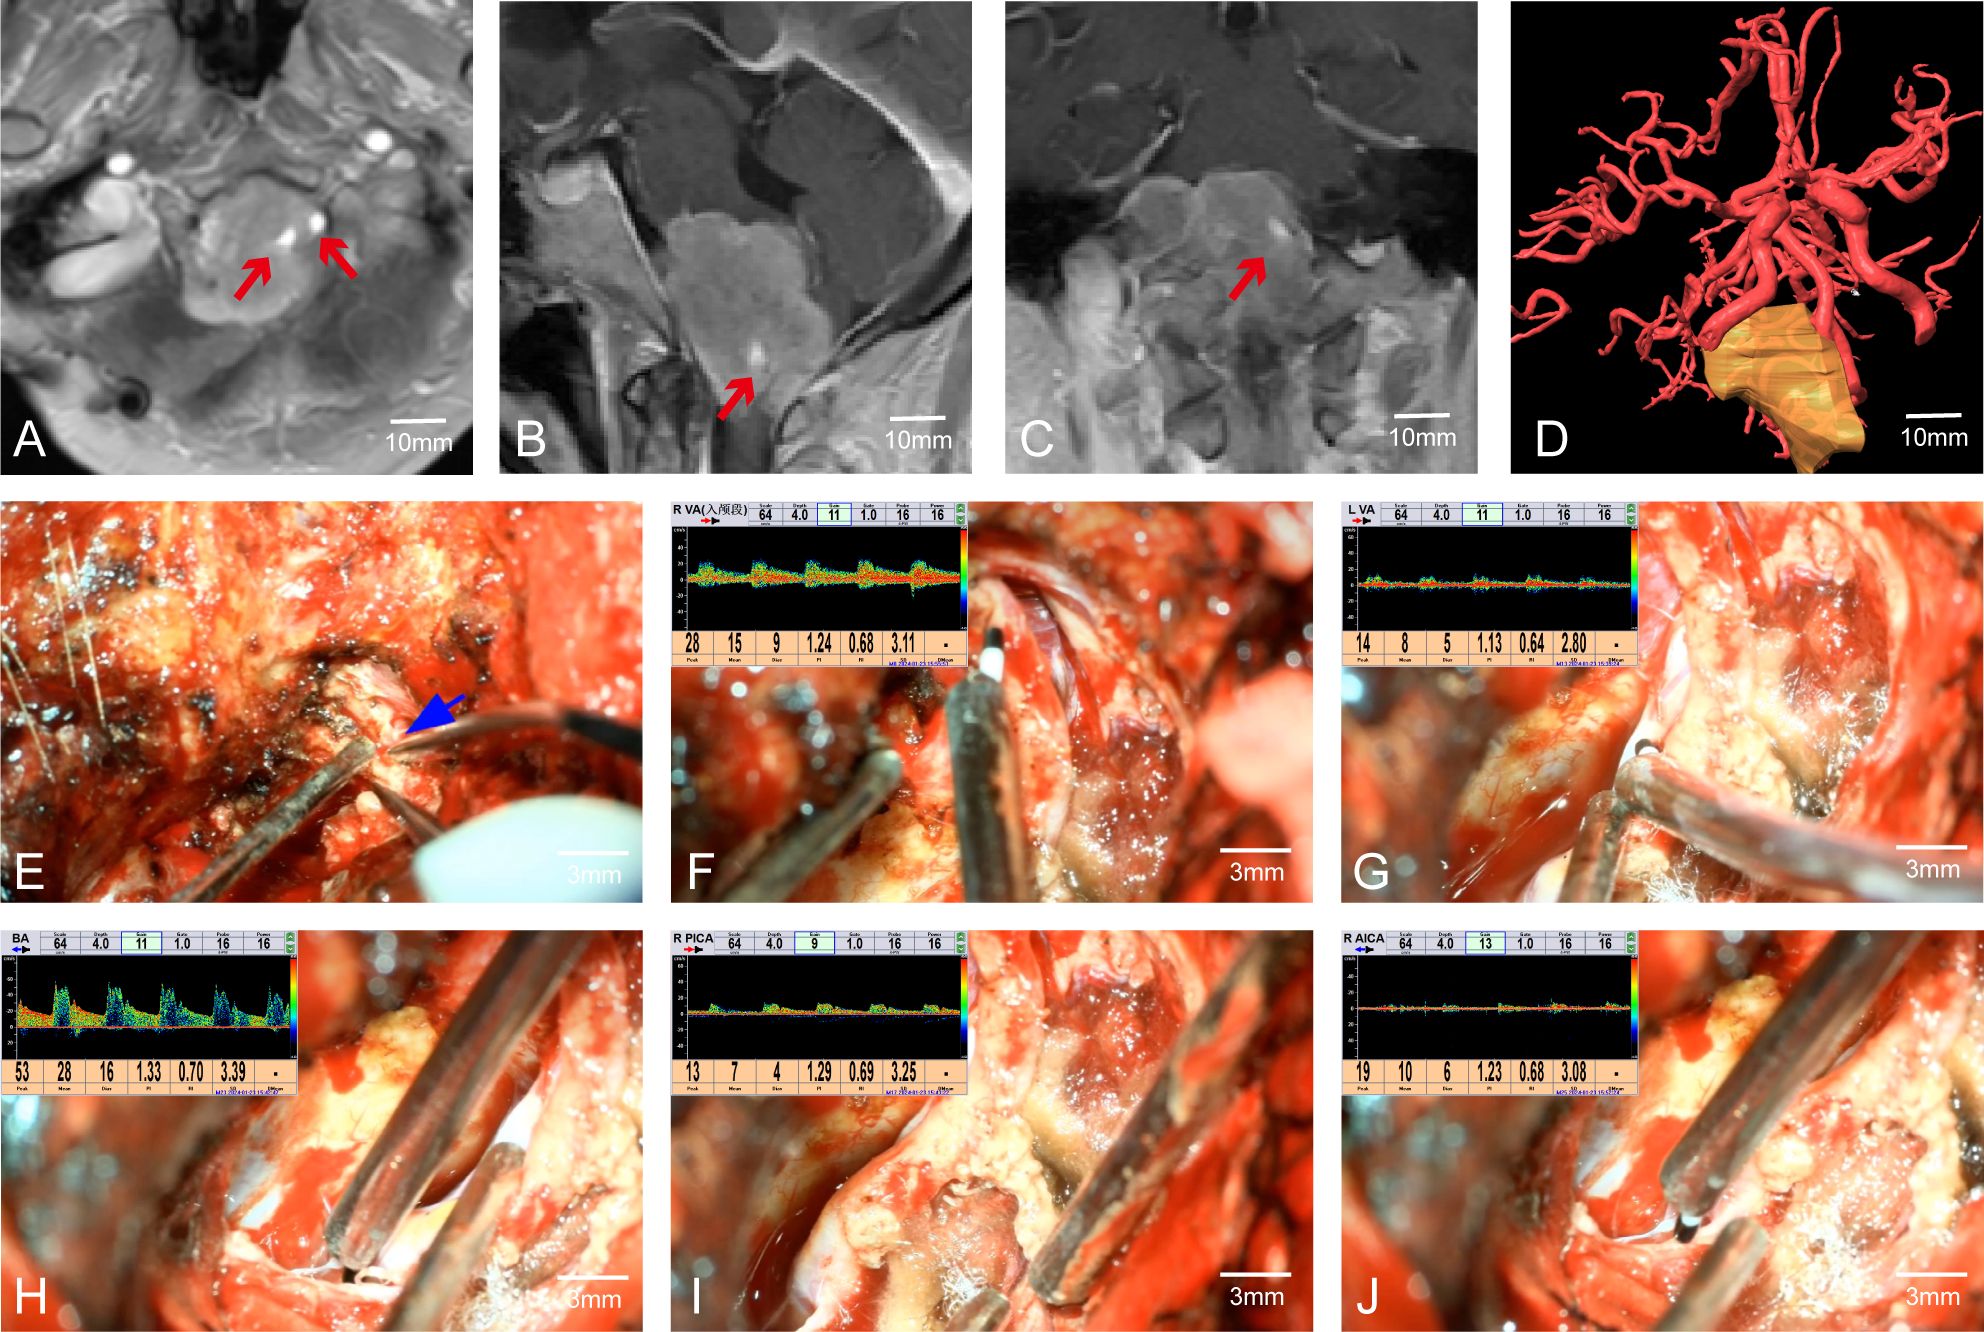

In Case 41, preoperative MRI indicated a tumor in the cerebellopontine angle region, causing severe compression of the medulla (Figures 3A–C). The patient had difficulty walking, accompanied by posterior cranial nerve symptoms such as choking on water, difficulty swallowing, and breathing issues, with bilateral lower limb muscle strength at grade II and bilateral upper limb muscle strength at grade IV. MRA suggested the tumor encased both vertebral arteries (VAs). Through multimodal fusion, we found the tumor encased the right VA and was closely related to the left VA (Figure 3D). This case represents a typical and challenging scenario of skull base tumors with vascular encasement.

Figure 3. Case 41. (A–C) MRA indicates that the tumor envelopes the bilateral vertebral arteries. (D) Preoperative multimodal fusion. (E) The location of the vertebral artery before the operation. (F–J) Postoperatively, MVD is used to confirm the location and patency of the vertebral artery and its branch vessels.

During craniotomy, it was difficult to distinguish the tumor from the blood vessels (Figure 3E). We used MVD to detect and identify the courses of both VAs, confirming the relationship between the VAs and the tumor as shown preoperatively by multimodal fusion. This cross-validation allowed us to protect the blood vessels well. Without MVD assistance, safely dissecting the tumor from the encased right VA would have been extremely challenging and posed a high risk of vascular injury. Post-tumor resection, re-detection of the VAs showed good pulsatile blood flow in the VAs and surrounding branches (Figures 3F–J). The patient had a good prognosis with significant relief of medulla compression.